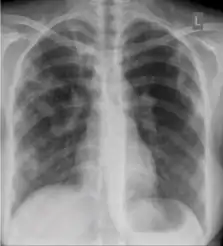

Chest x-ray showing coarse reticulonodular densities on the lower right lung of post-primary pulmonary TB.